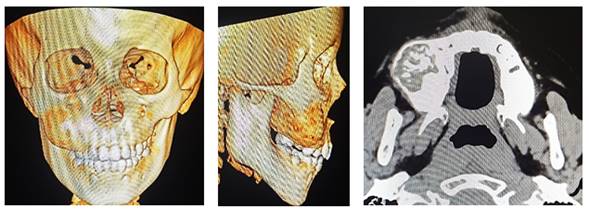

La tomografía computarizada de macizo facial con contraste se evidencia imagen hiperdensa heterogénea de bordes regulares que se extiende desde fosa canina hasta región pterigomaxilar inferior a agujero infraorbitario (Figura 2).

Figura 2. Tomografía con reconstrucción 3-D y Axial con contraste.